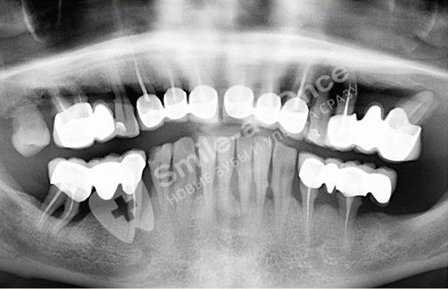

Патогенез пародонтоза

При пародонтозе изменения затрагивают невидимую для глаз человека часть — костную ткань челюсти. Изменения, которые происходят в ней, приводят к подвижности зубов и как результат — их удалению. На уровне кости изменения затрагивают процесс образования костной ткани: новая ткань на фоне разрушения не успевает восстановиться с помощью специальных клеток, строящих ее. Ткань кости челюсти постепенно убывает. Этот процесс виден только на рентгенограмме челюстей. [5]

Степень разрушения кости челюстей исследуют с помощью рентгенологического исследования (панорамная рентгенография, компьютерная томография), по которой можно различить стадии пародонтоза. Плотность костной ткани изучают с помощью эхоостеометрии. Изучение состава слюны и микрофлоры полости рта дает большие возможности в терапии пародонтоза. [8]

Происходит убыль костной ткани вплоть до 1/2 высоты зубного корня за счет разрушения (деструкции) межальвеолярных перегородок. Появляются очаги остеопороза – кость становится все менее плотной. Наблюдается достаточно ярко выраженная потеря ткани.

- компьютерная томография для оценки существующего объема костной ткани в нескольких измерениях,